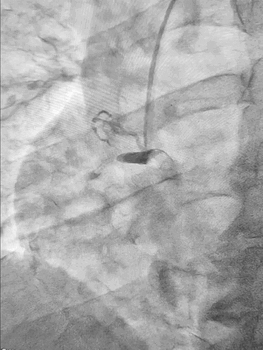

Ургентна коронароангіографія - LCA- помірно виражена, без явищ стенозування на всьому протязі. Відмічаються поодинокі колатеральні гілки в дистальний сегмент RCA. RCA- помірно виражена. Відмічається дисекція інтими в ділянці гирла. В проксимальному сегменті - гілок не виявлено. В середньому сегменті - оклюзована за рахунок великої кількості тромботичних мас.